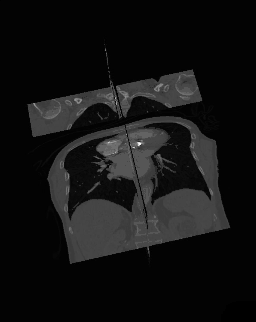

- 3D Multi-Planar Reconstruction

- A final variant on the MPR theme is the generation of a three-dimensional display showing all three orthogonal projections combined so that a defined point of interest locates the intersection of the planes, as illustrated in Figure 5.22.

- The point of intersection is located for illustrative purposes at the centre of the voxel data in the figure. It can typically be placed at any point in the 3D data using interactive controls. In addition, the perspective used for the rotating sequence can be manipulated interactively to improve the visualization of a region of interest. Note that the image sequence illustrated is one from a myriad of perspectives that can thus be generated. Note also that slice projections (e.g. MIPs) can be combined with this form of display to provide additional perspectives on a feature of interest.